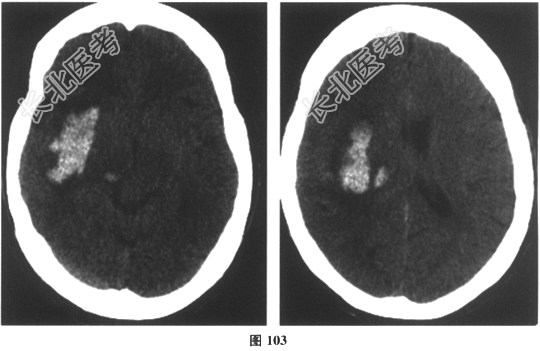

- 简答题6、[提示]急查颅脑CT,结果如图103所示。

该患者诊断为?